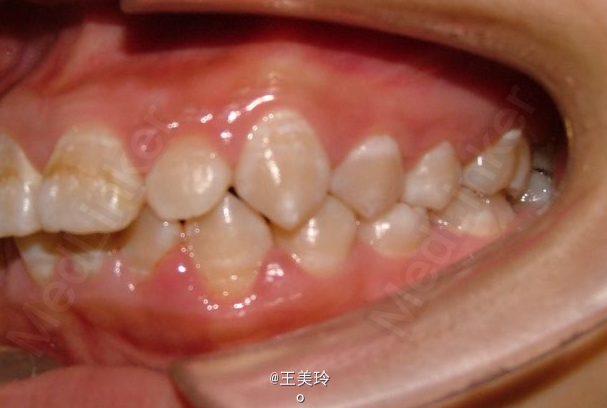

主诉:面突求矫治 既往史:无矫治史,无牙科治疗史,无外伤史,无过敏史,无口腔不良习惯,无家族遗传史 口腔检查:恒牙列,A7-B7;C7-D7。个别牙齿不齐 尖牙磨牙I类关系轻度深覆合深覆盖 下颌中线右偏约2mm 双颌前突,突面型 关节无弹响无压痛

诊断:安氏I类双颌前突 矫治计划 1.MBT矫治技术 2.拔牙矫治,拔A4B4C4D4 3.闭隙曲,J勾内收前牙 4.矫治结束后尖牙,磨牙,覆合覆盖正常 5.面型有所改善